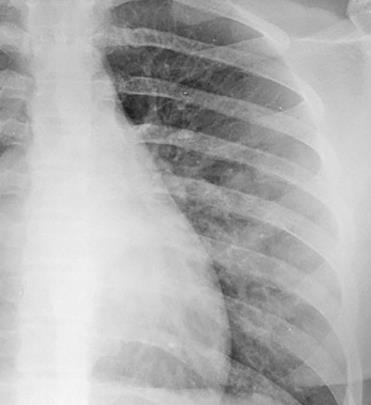

Pediatric COVID-19: MIS-C

Thoracic abnormalities

Cardiovascular abnormalities

Cardiomegaly

CHF or cardiogenic edema

Pulmonary parenchymal abnormalities

Lower lobe atelectasis

Bilateral opacities( ARDS)

Consolidation

Pleural abnormalities

Small pleural effusion

Mediastinal and hilar lymphadenopathy